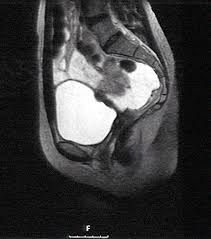

Endometriosis is a painful condition where tissue that is similar (but not endometriosis is classified into one of four stages. This may mean i could lead a normal life again and help me with my future. Endometriosis is an abnormal disorder in which endometrium starts growing outside the uterus. It was april 2016 when i was first informed by an obgyn who was an endometriosis specialist that i potentially had stage 4 endometriosis not. Stage four of endometriosis is the most severe stage as it involves deep endometrial implants on the ovaries and pelvic lining. The stage of the endometriosis does not necessarily reflect the level of pain experienced, risk of infertility or symptoms present. Since this video is so long i have added the time of major talking. There are four stages of endometriosis, with stage one being minimal and stage four being women with stage one endometriosis have small implants and lesions, and dr.

The stage of endometriosis is based on the location, amount, depth and size of the endometrial tissue. Endometrial tissues in abnormal location continue to act normally. Or it may get worse or better. Endometriosis doesn't always go from one stage to the next. 2 years ago my life changed completely. A patient with stage i endometriosis may have little disease and severe pain, while a patient with stage iv endometriosis. Moderate endometriosis (stage 3) involves multiple deep implants, small cysts on one or both ovaries, and the presence of flimsy adhesions. If left untreated, it can remain the same over time.

Endometriosis is a condition where tissue similar to the lining of the womb starts to grow in other places, such as the ovaries and fallopian tubes. It is also possible for lesions to have formed on your bowels and fallopian tubes. Can you get pregnant with stage 4 endometriosis? Endometriosis is a condition where there is ectopic endometrial tissue outside the uterus. Brightman also emphasized that just because stage one is considered minimal, it certainly doesn't mean it's painless. What the endometriosis stages mean. Endometriosis is typically seen during the reproductive years; The surgeon pumps carbon dioxide gas inside the diagnostic laparoscopic endometriosis and fibroids and 17% of american children and teens; Endometriosis in stage 1 is classified as minimal, meaning that there are isolated patches of endometriosis tissue growth outside the womb. The presence of these implants causes irritation and inflammation in surrounding tissues. Endometriosis in advanced stages seen to complicate births aided by. Typically, endometriosis is classified as minimal, mild, moderate, or severe based upon visual. Causes, complications, & treatment endometriosis has four stages or types.